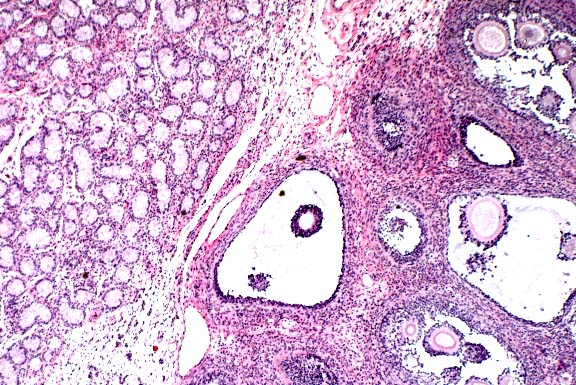

Contributor's Diagnosis and Comments: Ovotestis.

Chromosomal sex is normally determined at fertilization by the formation of either an XY or XX zygote. The Tdy gene on the Y chromosome encodes the protein testis-determining factor, which initiates testicular differentiation. Studies in mice have shown Tdy to be the only Y-linked gene necessary for testicular differentiation. Male phenotypic sexual determination results from the testicular secretion of 1) Müllerian inhibiting substance (MIS), which causes the Müllerian duct system to regress, and 2) testosterone, which promotes development of the vas deferens and epididymides from the Wolffian ducts. In the absence of the Y chromosome and Tdy gene, the default pathway to female gonadal sexual differentiation is initiated.

Hermaphrodites are classified according to the morphology of

the gonads present. A true hermaphrodite has at least one gonad

containing ovarian and testicular tissue (i.e. an ovotestis) or

has one male and one female gonad. A pseudohermaphrodite has gonads

of one sex and accessory reproductive organs of the opposite sex.

A male pseudohermaphrodite has testes and female accessory sex

organs; a female pseudohermaphrodite has ovaries and male accessory

reproductive organs.